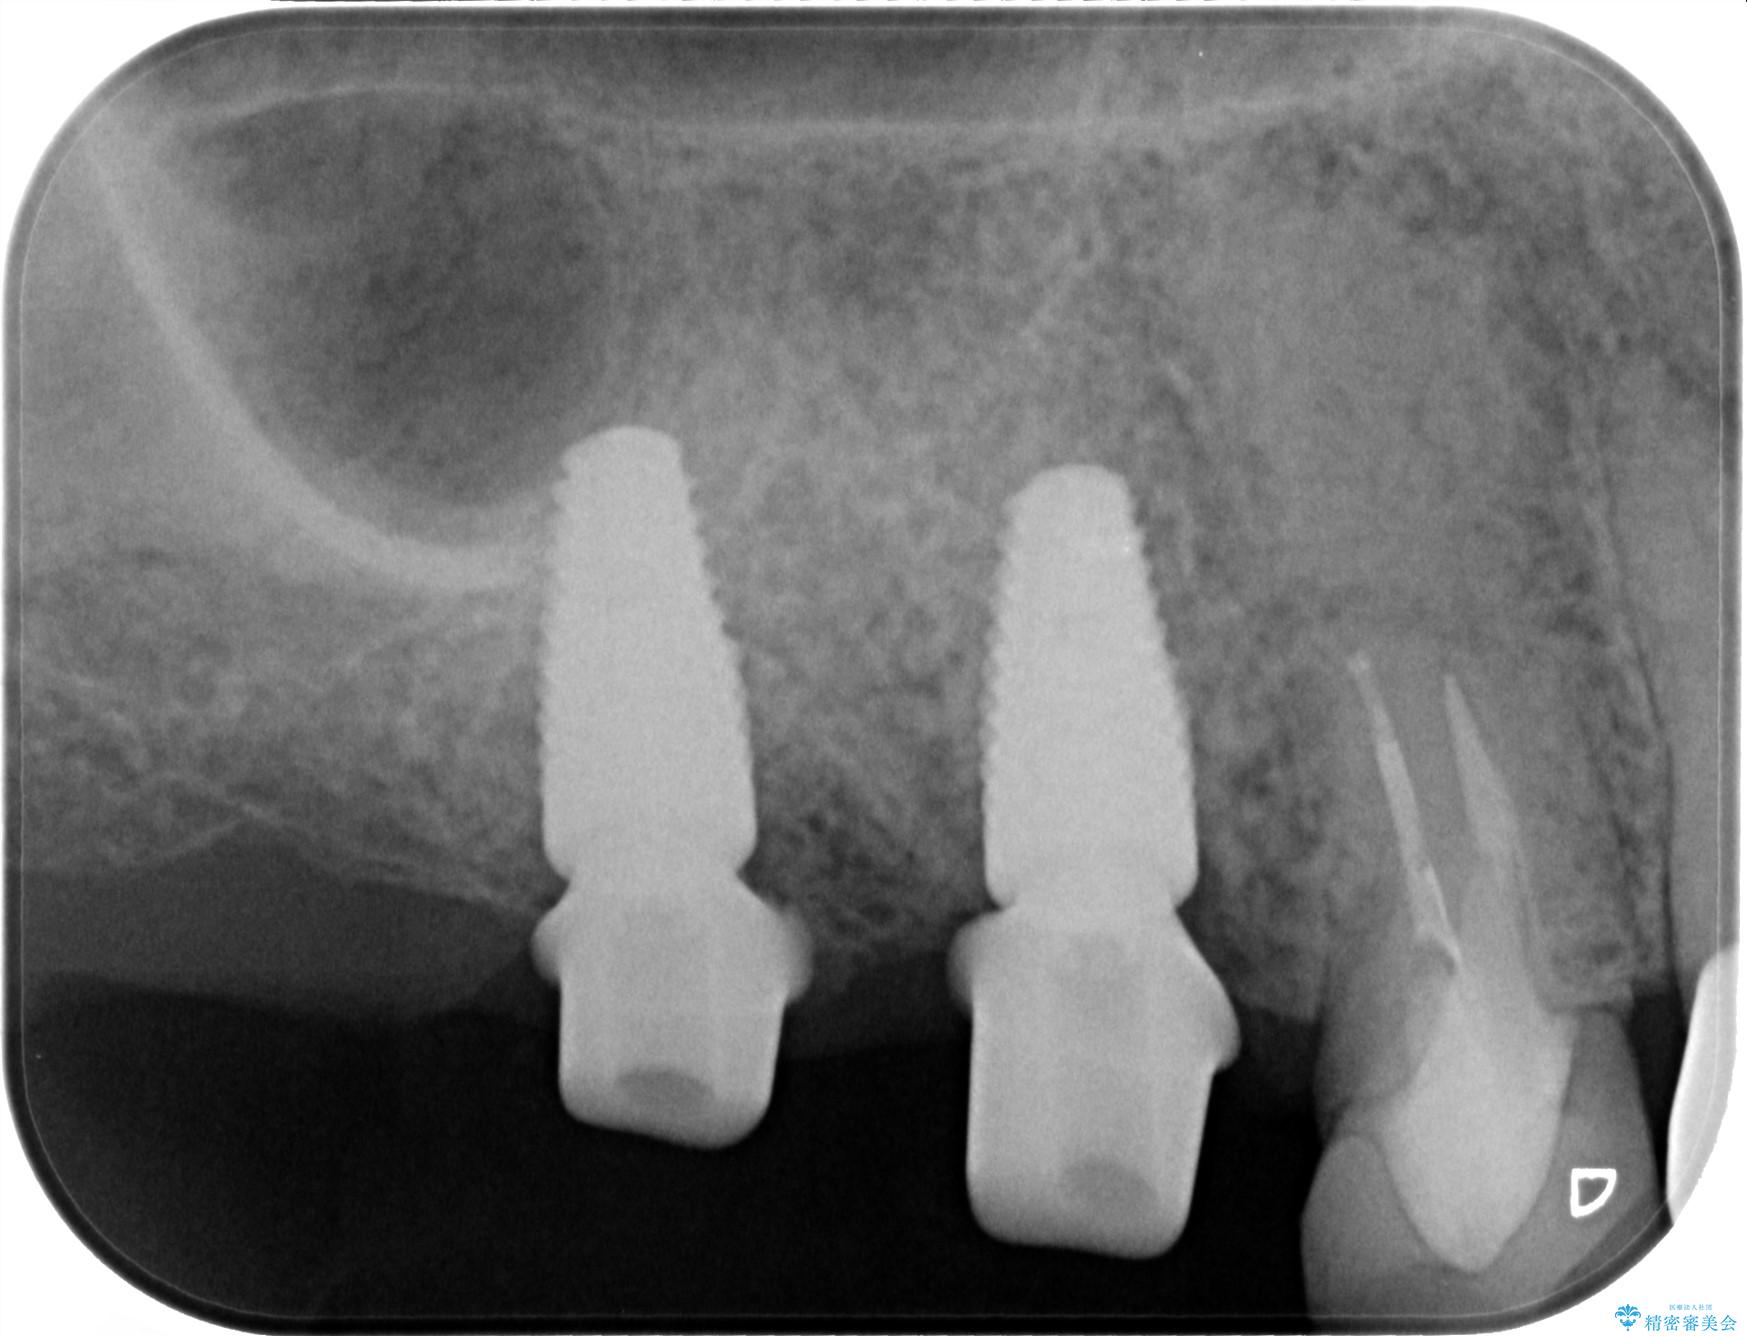

- 歯を抜いたまま放置してしまい、「やはりしっかりと噛めるような状態にしてほしい」とインプラント治療を希望され来院されました。

人工歯根であるインプラントを埋入することで奥歯でまたしっかりと噛める咬合機能を回復します。

- 88万円(インプラント×2・仮歯×2・チタンカスタムアバットメント×2・ジルコニアクラウン×2)費用は治療当時の料金となります